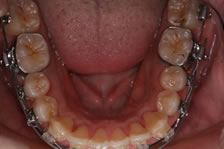

PAOO(歯周外科処置)術中写真:下顎

奥歯の骨の表面に小さく傷をつけて活性化させます。その上に骨の形成を促進させるため骨移植材を置きます。

下の智歯(おやしらず)は左右とも、術中に抜歯しました。